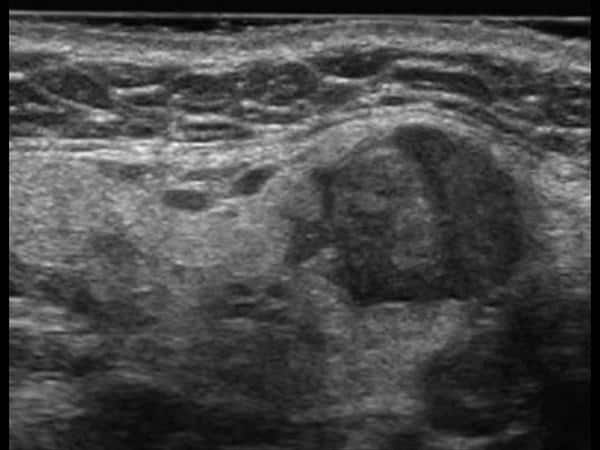

U tuyến nước bọt

» Thông tin: Nữ giới – 60 tuổi.

» Lâm sàng: Khối vùng góc hàm.

# Di căn tuyến nước bọt dưới hàm.